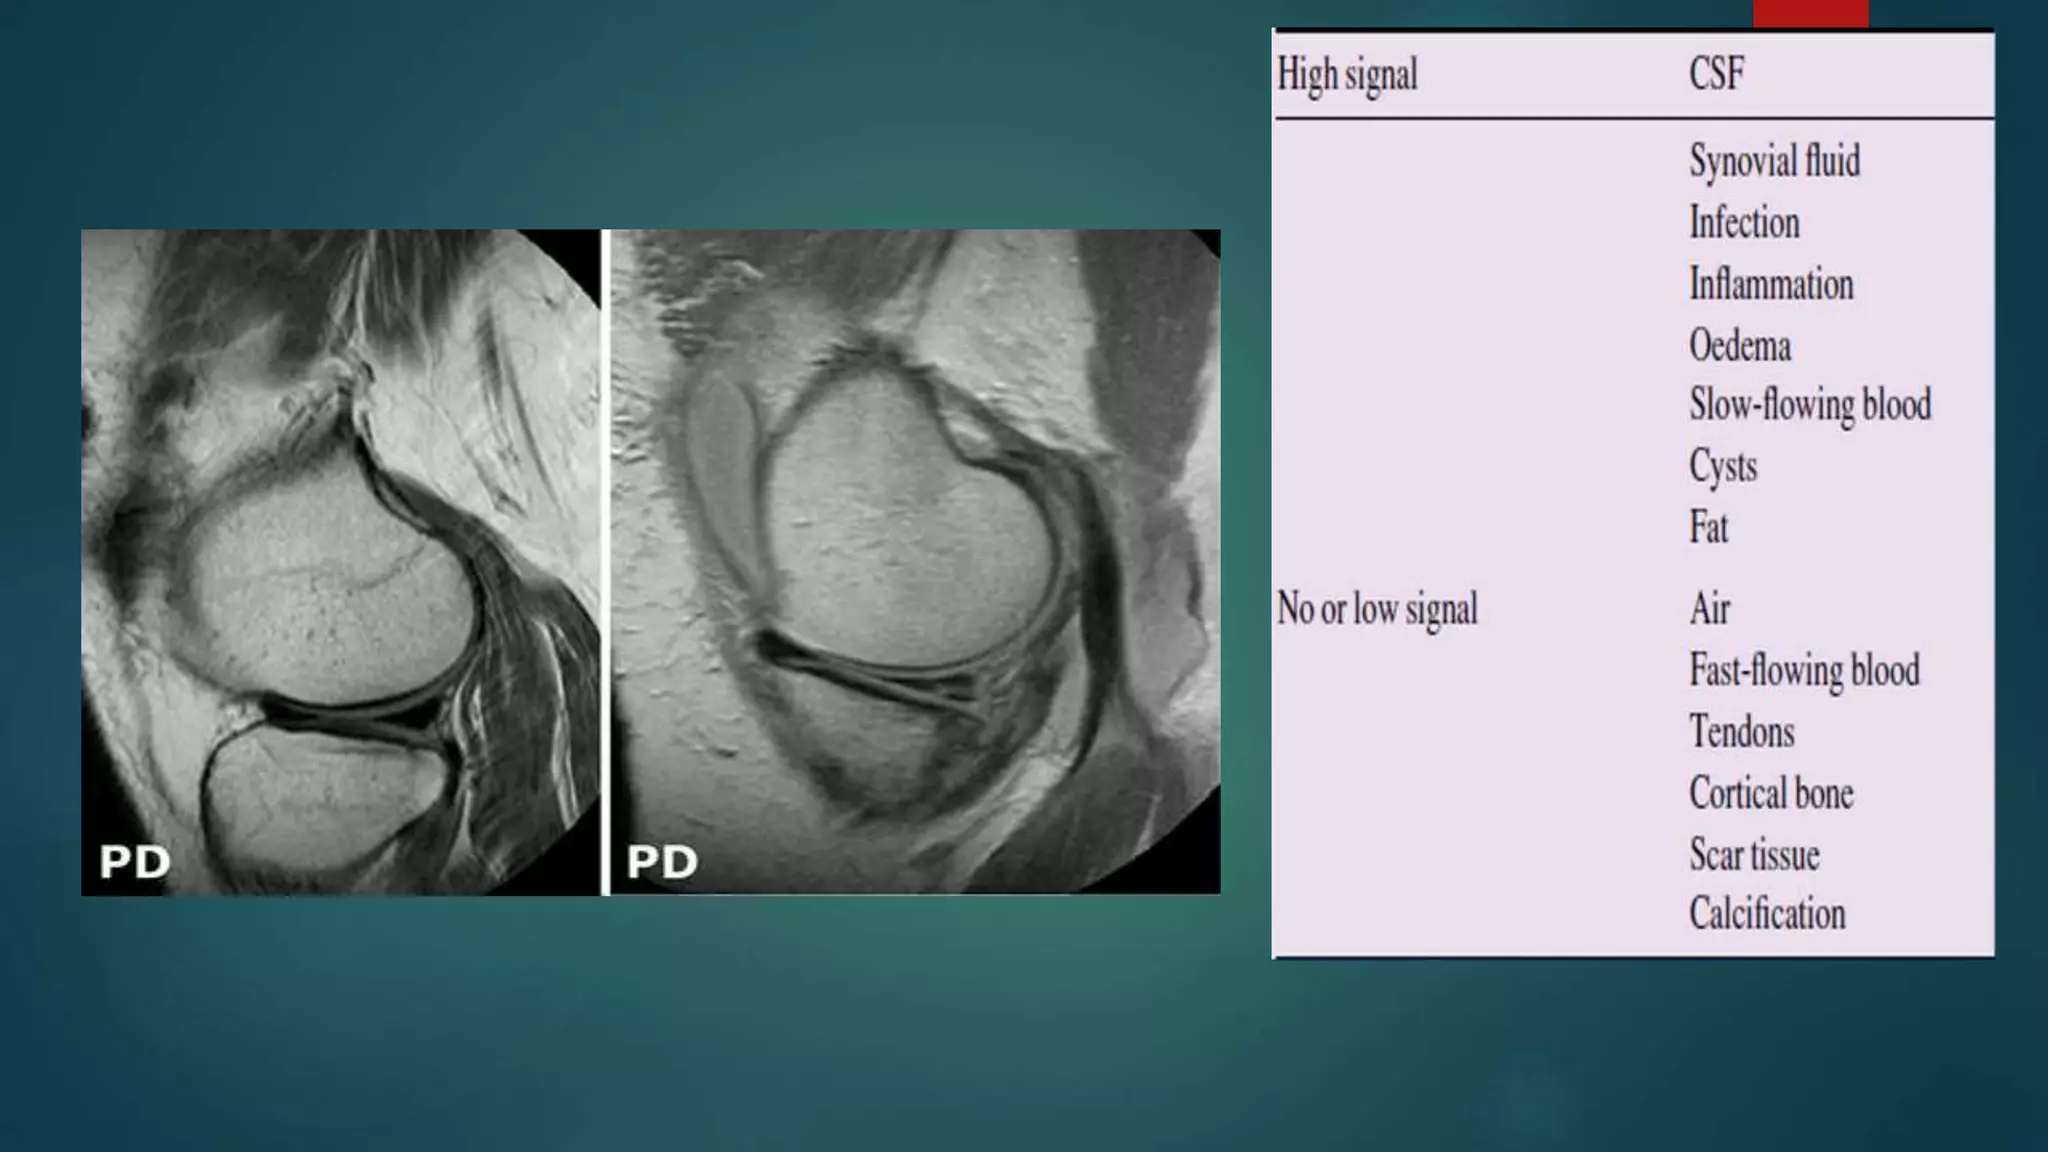

 A tissue has high signal (white, hyperintense) if it has large TM

 A tissue has a low signal (black, hypointense) – vice versa

 A tissue has an intermediate signal (grey, isointense) - medium

TM

PROTON DENSITY WEIGHTED IMAGING

Differences in the proton densities (number of hydrogen

protons in the tissue) demonstrated.

 Both T1 and T2 effects diminished - T1 by long TR and T2 short

TE .

 Tissues with low proton density dark (low signal, hypointense)

because the low number of protons results in a small

component of TM.

 Tissues with a high PD are bright (high signal, hyperintense